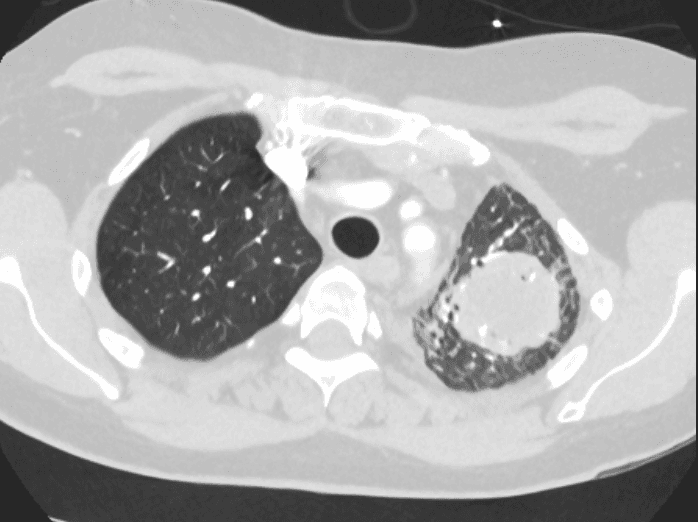

Laboratory data: hemoglobin 10.4 g/dL, WBC 7.6 x 10^9/L, platelets 138 x 10^9/L, LDH 418 U/L (elevated), uric acid 7.2 mg/dL. Serum creatinine and tacrolimus trough are within target range. CT of the chest with contrast reveals a 4.2 cm heterogeneous mass in the left upper lobe with associated mediastinal lymphadenopathy.

CT chest with contrast: 4.2 cm heterogeneous left upper lobe mass with associated mediastinal lymphadenopathy.